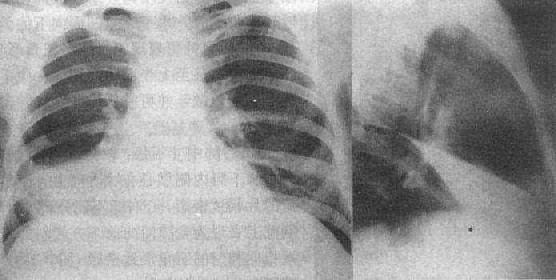

2)右肺中叶不张:较为常见,后前位表现为右肺下野内侧靠心右缘现上界清楚下界模糊的片状致密影,心右缘不能分辨(图3-1-9)。侧位上表现为自肺门向前下方倾斜的带状或尖端指向肺门的三角形致密影(图3-1-9)。上、下叶可有代偿性肺气肿。

右肺中叶肺不张(正、侧位)

图3-1-9 右肺中叶肺不张(正、侧位)